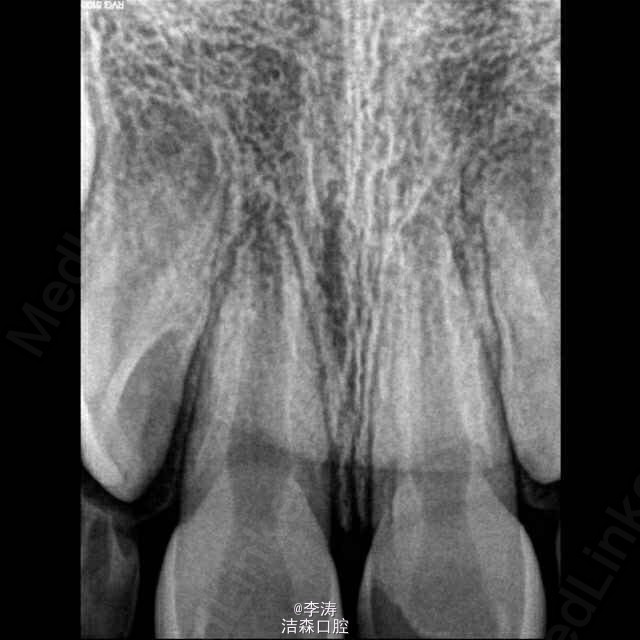

一7岁男孩上前牙外伤1小时就诊,检查,21牙牙冠大面积缺损未露髓,11牙牙釉质小部分缺损,牙龈红肿出血,未及明显松动,52,62牙未脱落,x线片未见明显根折,11牙可见根尖暗影,两牙根管口均粗大。 调颌后建议患者观察两周,若无牙髓症状,牙髓活力正常,可直接充填缺损。若出现牙髓症状,或者牙髓活力丧失,行根尖诱导成形术。 思考,此病例受伤牙未刚萌出恒牙,若牙髓失去活力,髓腔如此大,即使诱导成形成功将来能承担打桩做冠发挥咀嚼的功能么? 此病例两侧乳牙均未脱落,如果前牙有II~III度松动,怎么固定???用乳牙结扎应该不可行吧?